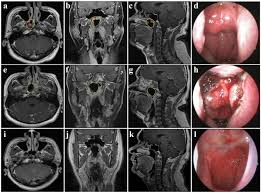

Basaloid Squamous Cell Carcinoma Arising In An Inverted Papilloma In The Nasal Cavity A Case Report And Review Sciencedirect

Basaloid Squamous Cell Carcinoma Arising In An Inverted Papilloma In The Nasal Cavity A Case Report And Review Sciencedirect from ars.els-cdn.com